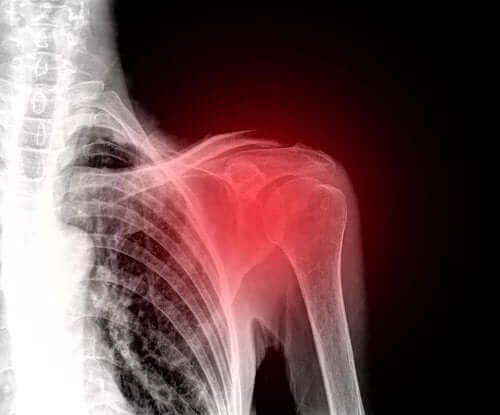

Een gescheurde schouderpees of een cuffruptuur is een verwonding die vaak de schouders van mensen van middelbare leeftijd aantast. Het is daarom momenteel een van de belangrijkste oorzaken van schouderpijn.

De symptomen die optreden zijn afhankelijk van de ernst van de blessure. Het overheersende symptoom is echter pijn in de schouder. Daarnaast worden alle bewegingen van dit gewricht beperkt.

Diagnose

Ook gebruikt men aanvullende tests zoals echografie of magnetische resonantie beeldvorming. Dit doen ze omdat echografie hen in staat stelt je pezen en spieren te evalueren terwijl je beweegt. Bovendien is het een betaalbare en niet-invasieve test.